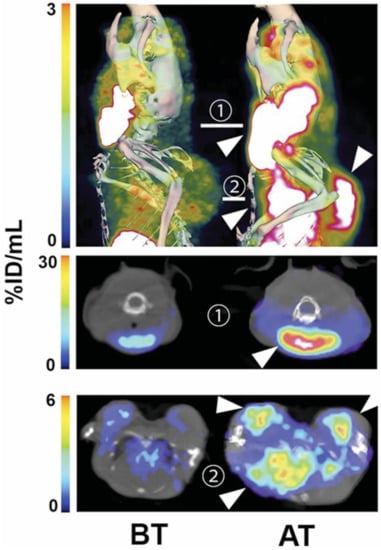

- Neves, A.A.; Xie, B.; Fawcett, S.; Alam, I.S.; Witney, T.H.; de Backer, M.M.; Summers, J.; Hughes, W.; McGuire, S.; Soloviev, D.; et al. Rapid Imaging of Tumor Cell Death In Vivo Using the C2A Domain of Synaptotagmin-I. J. Nucl. Med. 2017, 58, 881–887. [Google Scholar] [CrossRef]

- Xie, B.; Tomaszewski, M.R.; Neves, A.A.; Ros, S.; Hu, D.E.; McGuire, S.; Mullins, S.R.; Tice, D.; Sainson, R.C.A.; Bohndiek, S.E.; et al. Optoacoustic Detection of Early Therapy-Induced Tumor Cell Death Using a Targeted Imaging Agent. Clin. Cancer Res. 2017, 23, 6893–6903. [Google Scholar] [CrossRef] [PubMed]